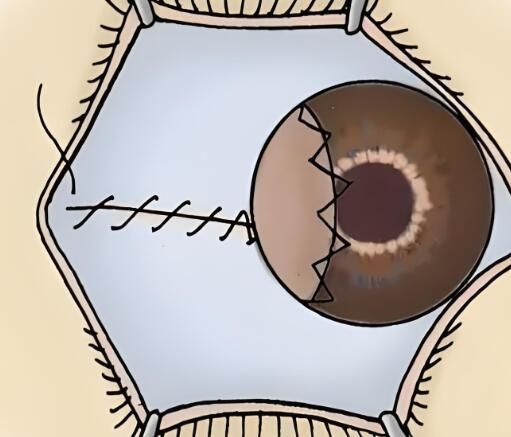

第六步:缝合和愈合

移植完角膜后,医生会使用细小的缝线将角膜固定在原位。这些缝线通常会自行吸收,在愈合过程中起到稳定角膜的作用。患者需要注意保持眼部清洁,并按医生的建议使用消炎药眼药水和抗生素眼药膏。